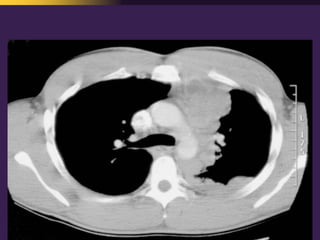

This document discusses mediastinal pathology using a compartmental approach. It describes the anatomy of the mediastinum and divides it into anterior, middle, and posterior compartments. Each compartment contains different structures and has a characteristic distribution of lesions. For example, 50% of lesions occur in the anterior compartment, which contains the thymus. The thymus is the most common site of lesions in the anterior compartment. Thymomas are the most common epithelial tumors of the thymus and mediastinum.